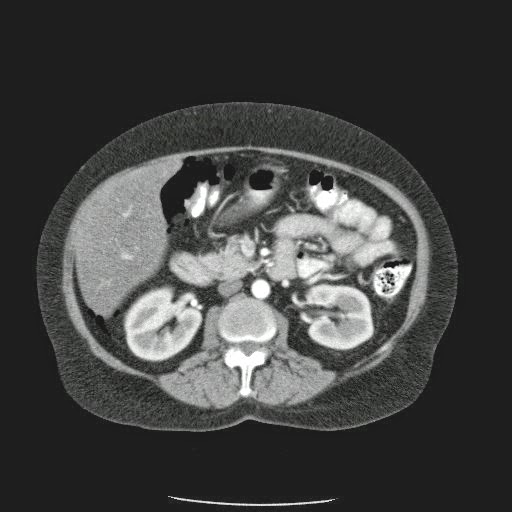

- ¿Hallazgos Escanografia?

2. Hay una colección de la pared abdominal en el flanco derecho, que realza en la periferia con el contraste, e intraabdominal tiene aire pero no me parece colección intraabdominal porque la grasa no está alterada.